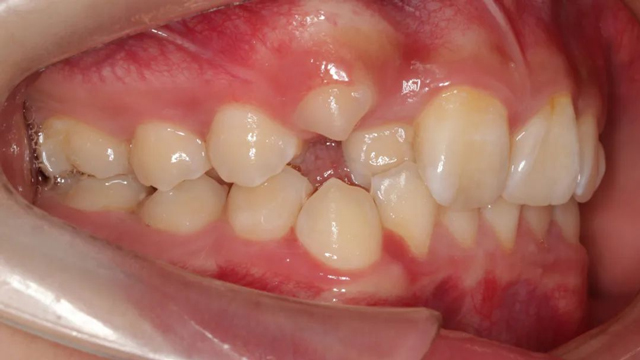

該病例的治療周期長達三年,跨替牙期和年輕恒牙期。治療結束時,小患者收獲了一口整齊美觀的牙齒,也從滿臉稚氣的孩童長成了青蔥少年。

2024年9月(矯正結束后口內照)

“隱形矯正一般2-3月復診一次,從節約時間來說很受家長青睞,但前提是小朋友要有很好的依從性,這是獲得滿意效果的前提。案例中的這個小朋友和家長與醫生的配合度非常高,這也是我們能治療成功的必要因素。”